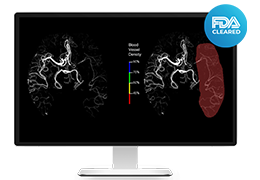

单屏工作效率与安全

ImageView 软件平台旨在通过提供以下功能,大幅提高影像效率和安全性:

所有 Carestream 影像采集产品通用的用户界面

减少屏幕切换,节省时间并增强工作流程

内置“安全设计”元素,提供入侵保护和防护